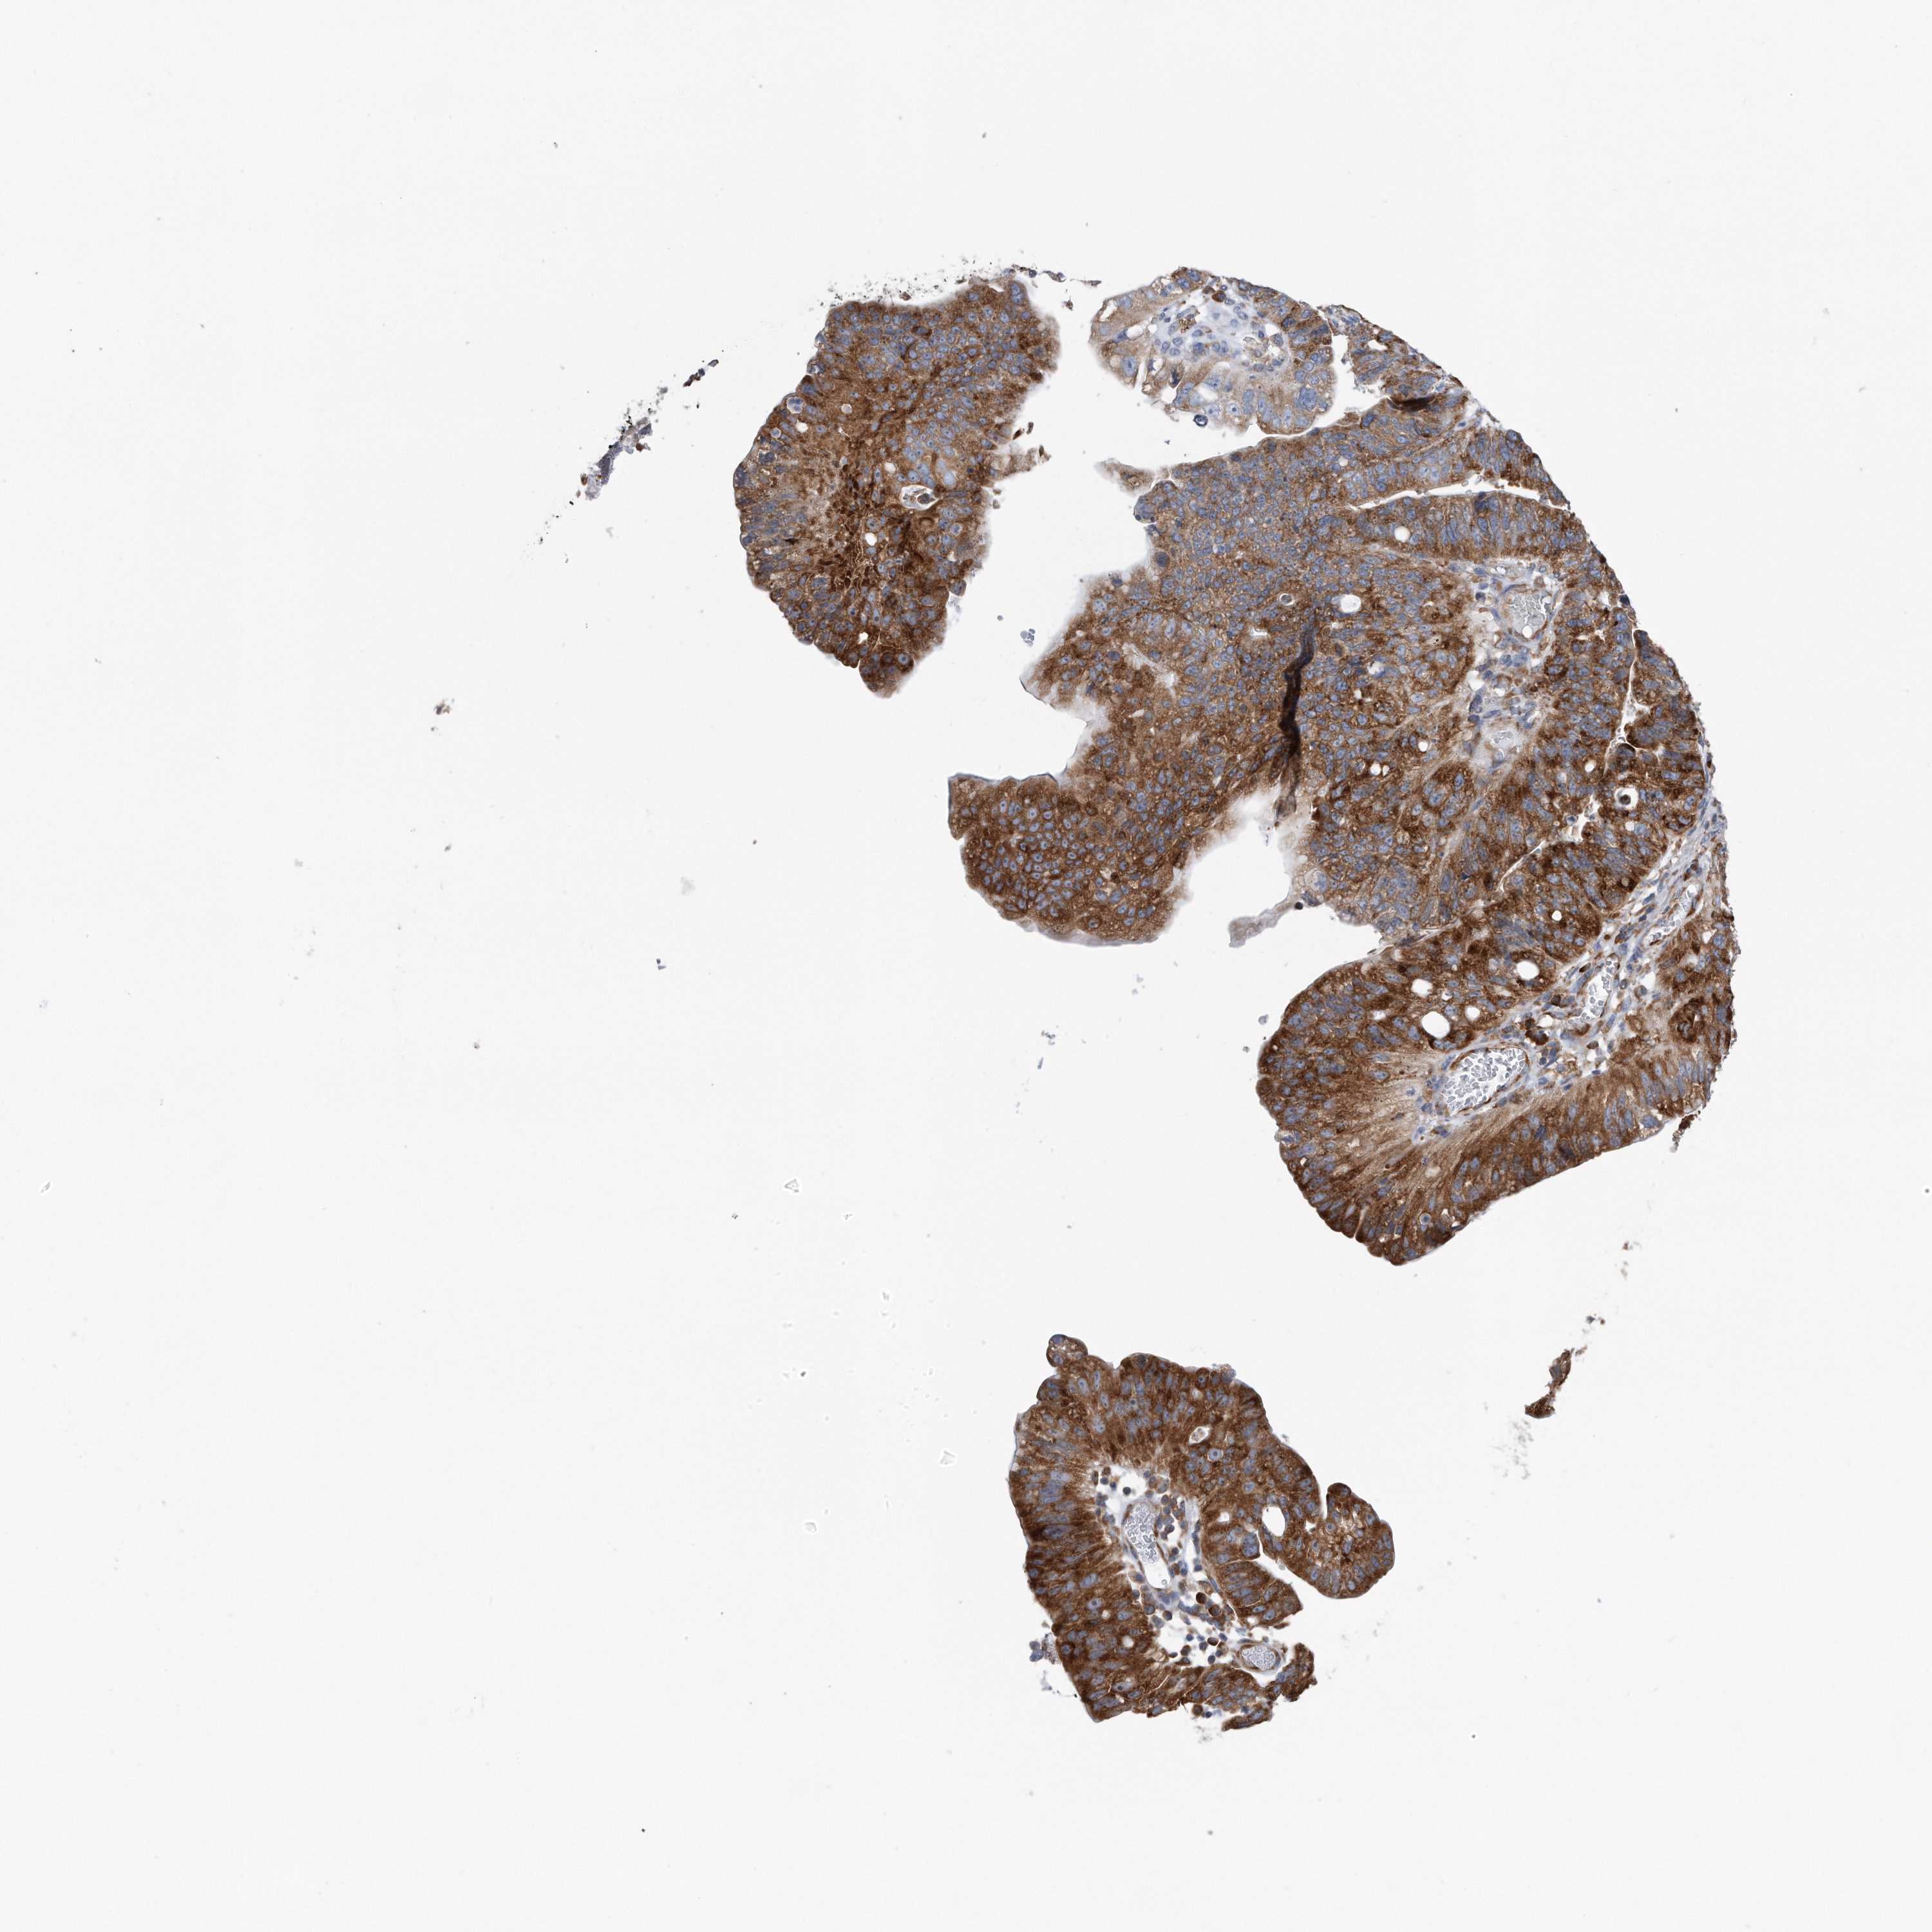

STOMACH CANCER - Protein expressioni

A mouse-over function shows sample information and annotation data. Click on an image to view it in a full screen mode. Samples can be filtered based on level of antibody staining by selecting one or several of the following categories: high, medium, low and not detected. The assay and annotation is described here.

Note that samples used for immunohistochemistry by the Human Protein Atlas do not correspond to samples in the TCGA dataset.

Antibody stainingi

Antibody staining in the annotated cell types in the current human tissue is reported as not detected, low, medium, or high, based on conventional immunohistochemistry profiling in selected tissues. This score is based on the combination of the staining intensity and fraction of stained cells.

Each image is clickable and will lead to virtual microscopy that enables deeper exploration of all samples and also displays staining intensity scores, fraction scores and subcellular localization as well as patient and tissue information for each sample.

Antibody CAB037301

Staining

High

Medium

Low

Not detected

Intensity

Strong

Moderate

Weak

Negative

Quantity

>75%

75%-25%

<25%

None

Location

Nuclear

Cytoplasmic/membranous

Cytoplasmic/membranous,nuclear

Adenocarcinoma, NOS